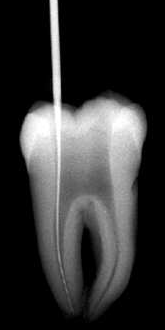

La apertura consiste en llegar a descubrir el techo de la cámara pulpar. Lo puede hacer con alta velocidad con una fresa o punta de diamante con abundante refrigeración acuosa.  Le aconsejamos que la apertura la realice con aislación relativa. Ver imagen izquierda.

La sensación al llegar a la cámara pulpar "es de caer en un vacío" ahí debe terminar la apertura propiamente dicha y debe pasar al proceso de rectificación de la cámara para el acceso a los conductos.